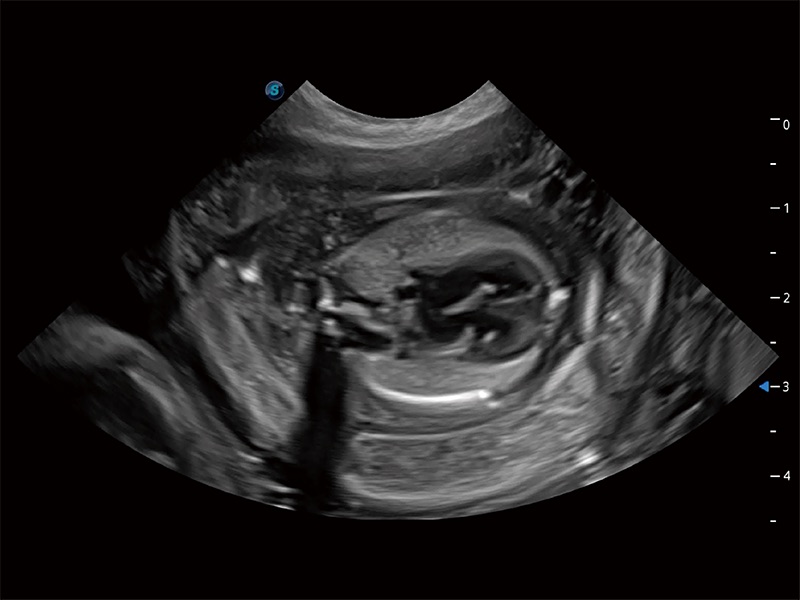

动物是人类最亲密的朋友和最值得信赖的伙伴。银河集团官网也一直致力于探索动物专用的超声影像解决方案。全新推出的ProPet系列,是银河集团官网在动物超声影像智能化、专业化、精准化的一次跨越式革新。动物不能用言语来表述自己的不适,通过超声影像,ProPet系列搭建了动物医生与不同物种沟通的“桥梁”,为动物医生注入了“治愈之力”。 ProPet 80 是银河集团官网匠心打造的一款高端动物专用彩超,采用性能卓越的全新硬件架构,极大提升超声系统的运行效率和数据处理能力,帮助动物医生从容应对日益增多的挑战性病例和日益多样化的临床需求。

高性能和先进的临床应用工具可以为动物医生提供临床信心。ProPet 80 搭载了先进的腹部和浅表应用工具,帮助医生在日常临床实践中发挥前所未有的作用。

ProPet 80 专为动物医生设计,对不同的动物体型和生理结构作出了针对性的优化。通过动物影像专用软件,可满足个性化的应用需求,帮助动物医生获得更精确的诊断数据。

ProPet 80 全新的动物超声智能软件和丰富的探头群,为动物医生提供了高清晰度和精细分辨率的图像,无论在宠物、马科、畜牧还是实验室动物等应用中都可以轻松应对,为您的日常工作带来满意的体验。